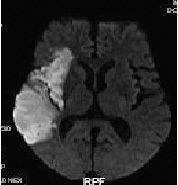

圖一

患者為一57歲男性,經由磁振造影的技術,不需注射顯影劑,即可清楚地看出右側中大腦動脈有嚴重的阻塞(上圖紅色圈圈標示的位置),在右圖中,白色的區域顯示出大腦中風的範圍。